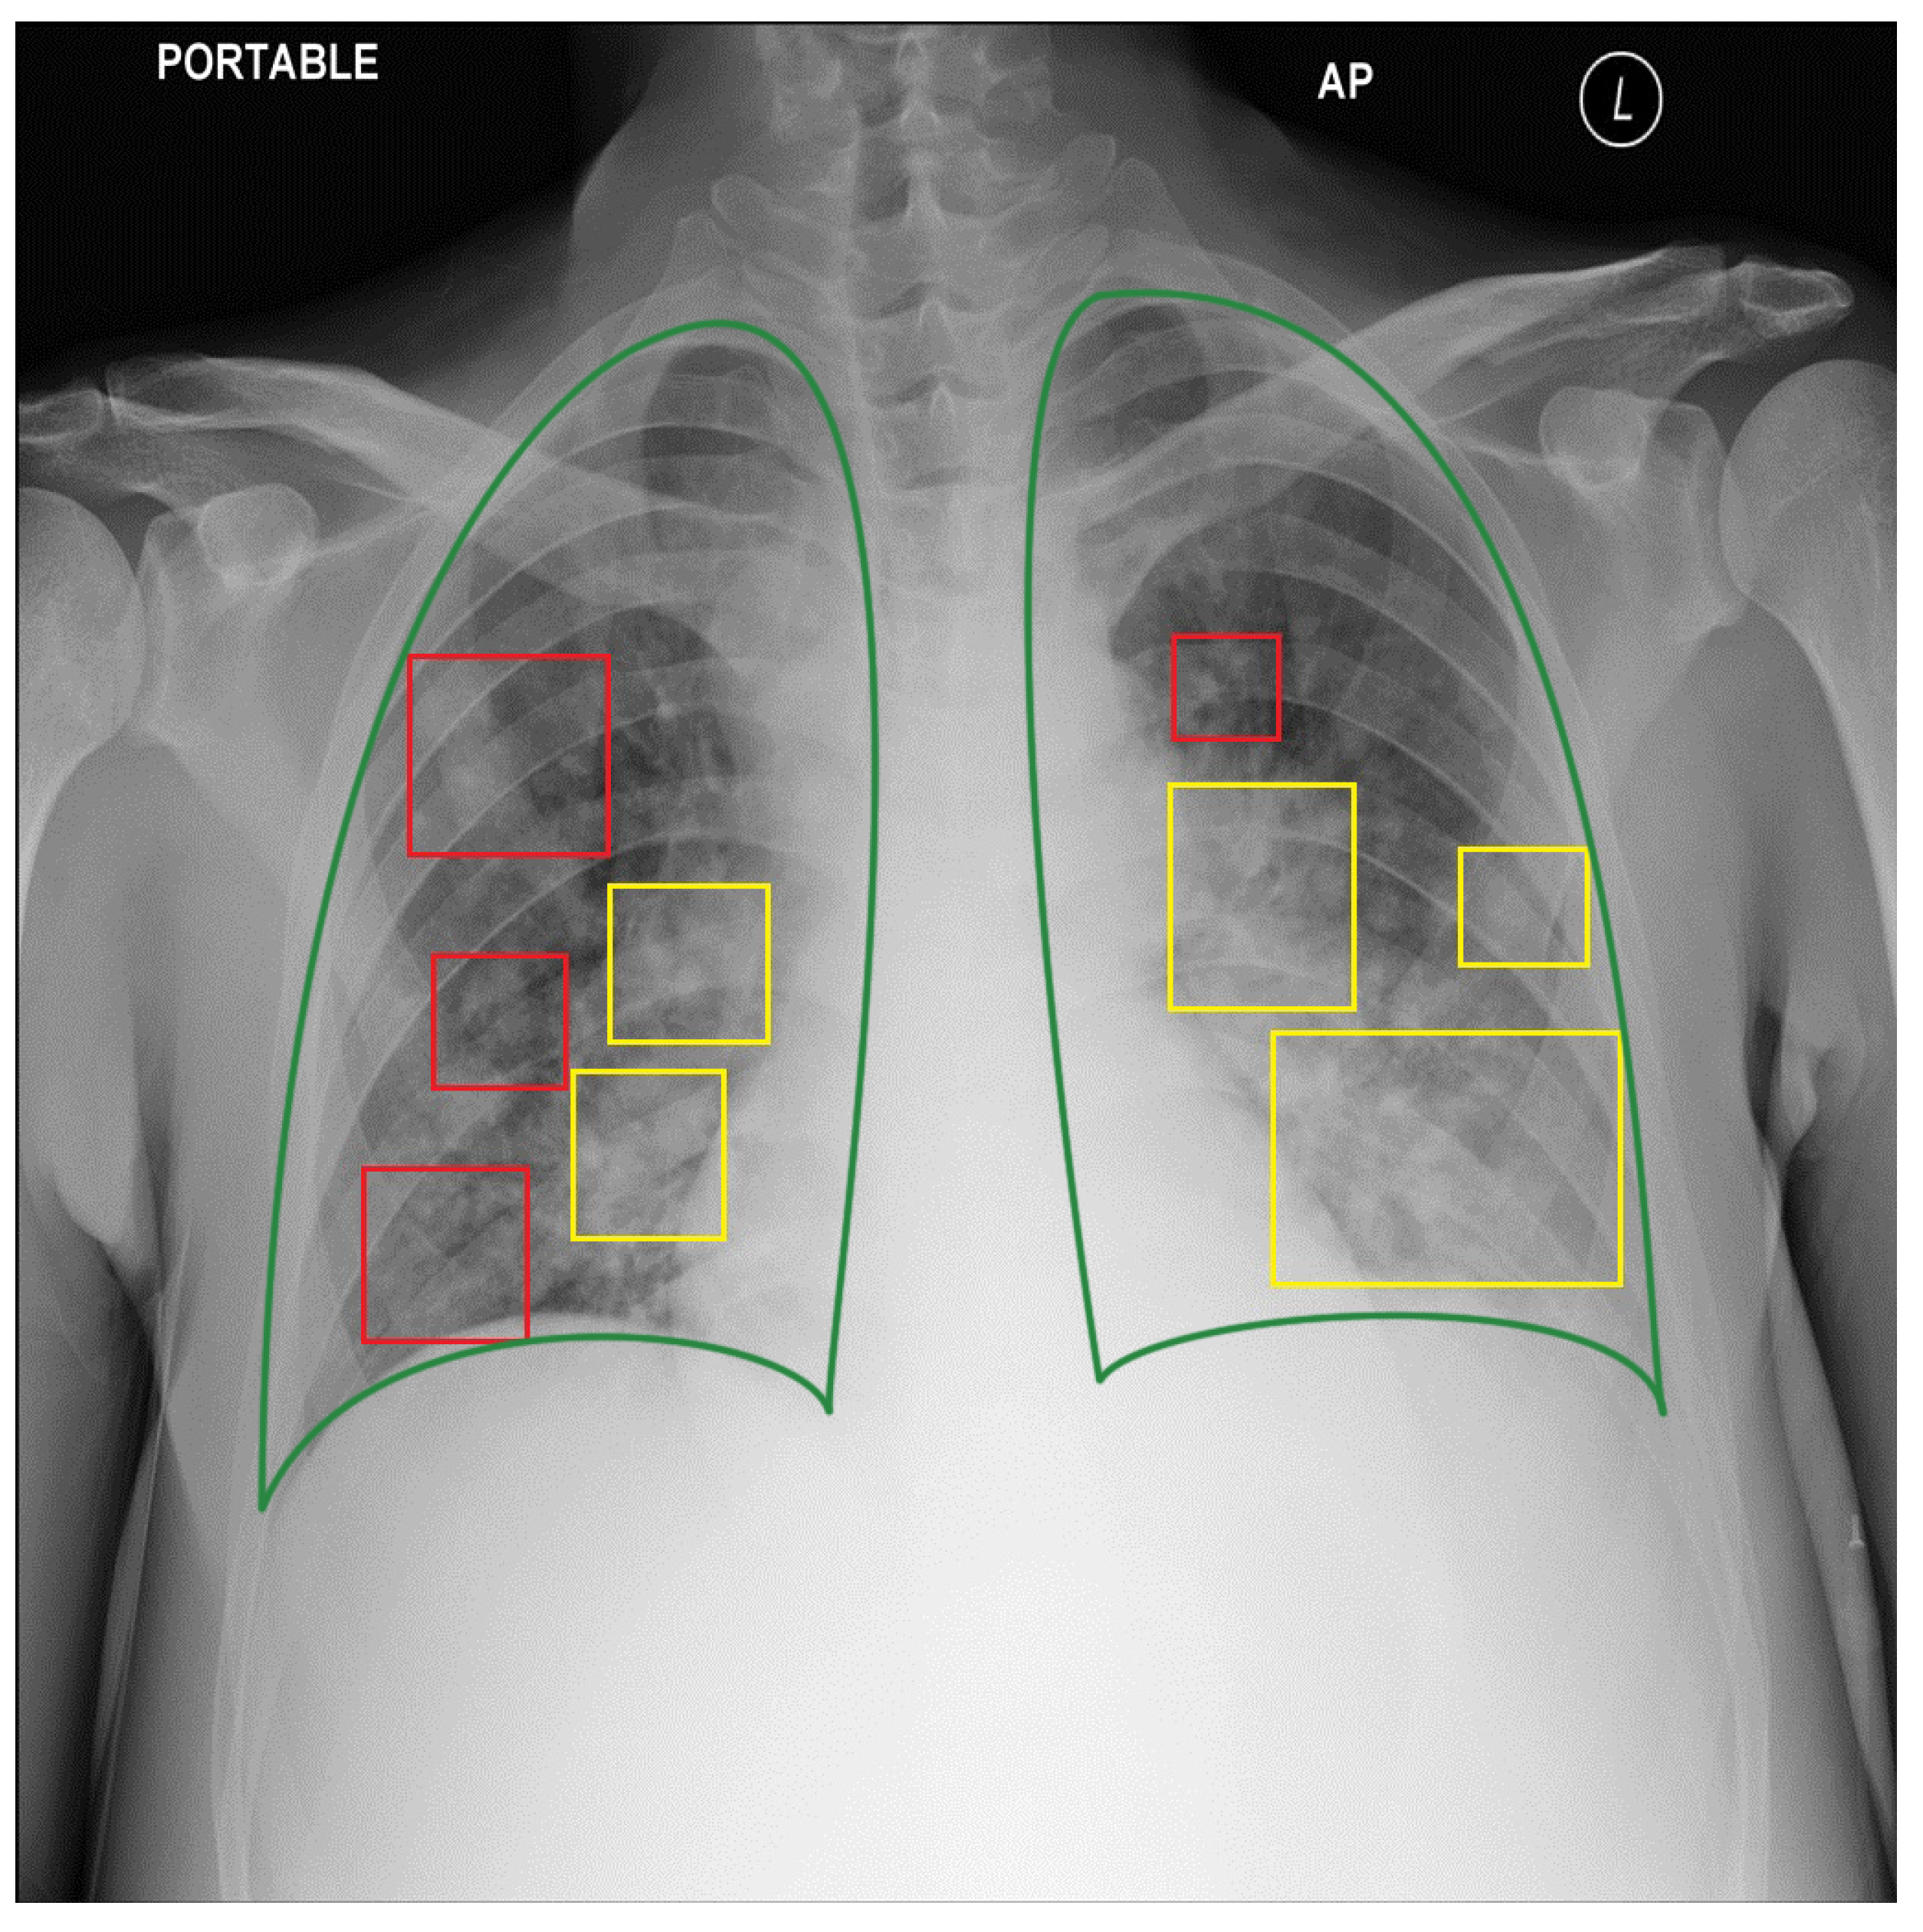

5.3. The Bias of Annotating Style

- We standardized three public datasets into the COCO format standard for a 2895 CXRs dataset with 7943 bounding box annotations for three types of COVID-19 lung lesions. We also reannotated the three public datasets to evaluate our model. Finally, we provide our 235 lung-lesion annotated COVID-19 CXRs with 1192 annotations collected since the first outbreak in a province of northern Vietnam. All evaluation data were annotated by our experienced physicians. These data significantly encourage reproducibility.